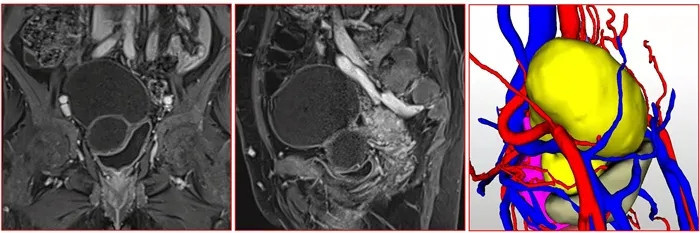

入院后肝胆外科经CT、核磁共振检查发现肝脏及盆腔有巨大肿块,考虑肝脏包虫病、盆腔包虫病或盆腔畸胎瘤的可能。因病灶与血管关系密切,盆腔肿块性质待定,需多学科联合会诊决定治疗方案。

盆腔包虫病灶